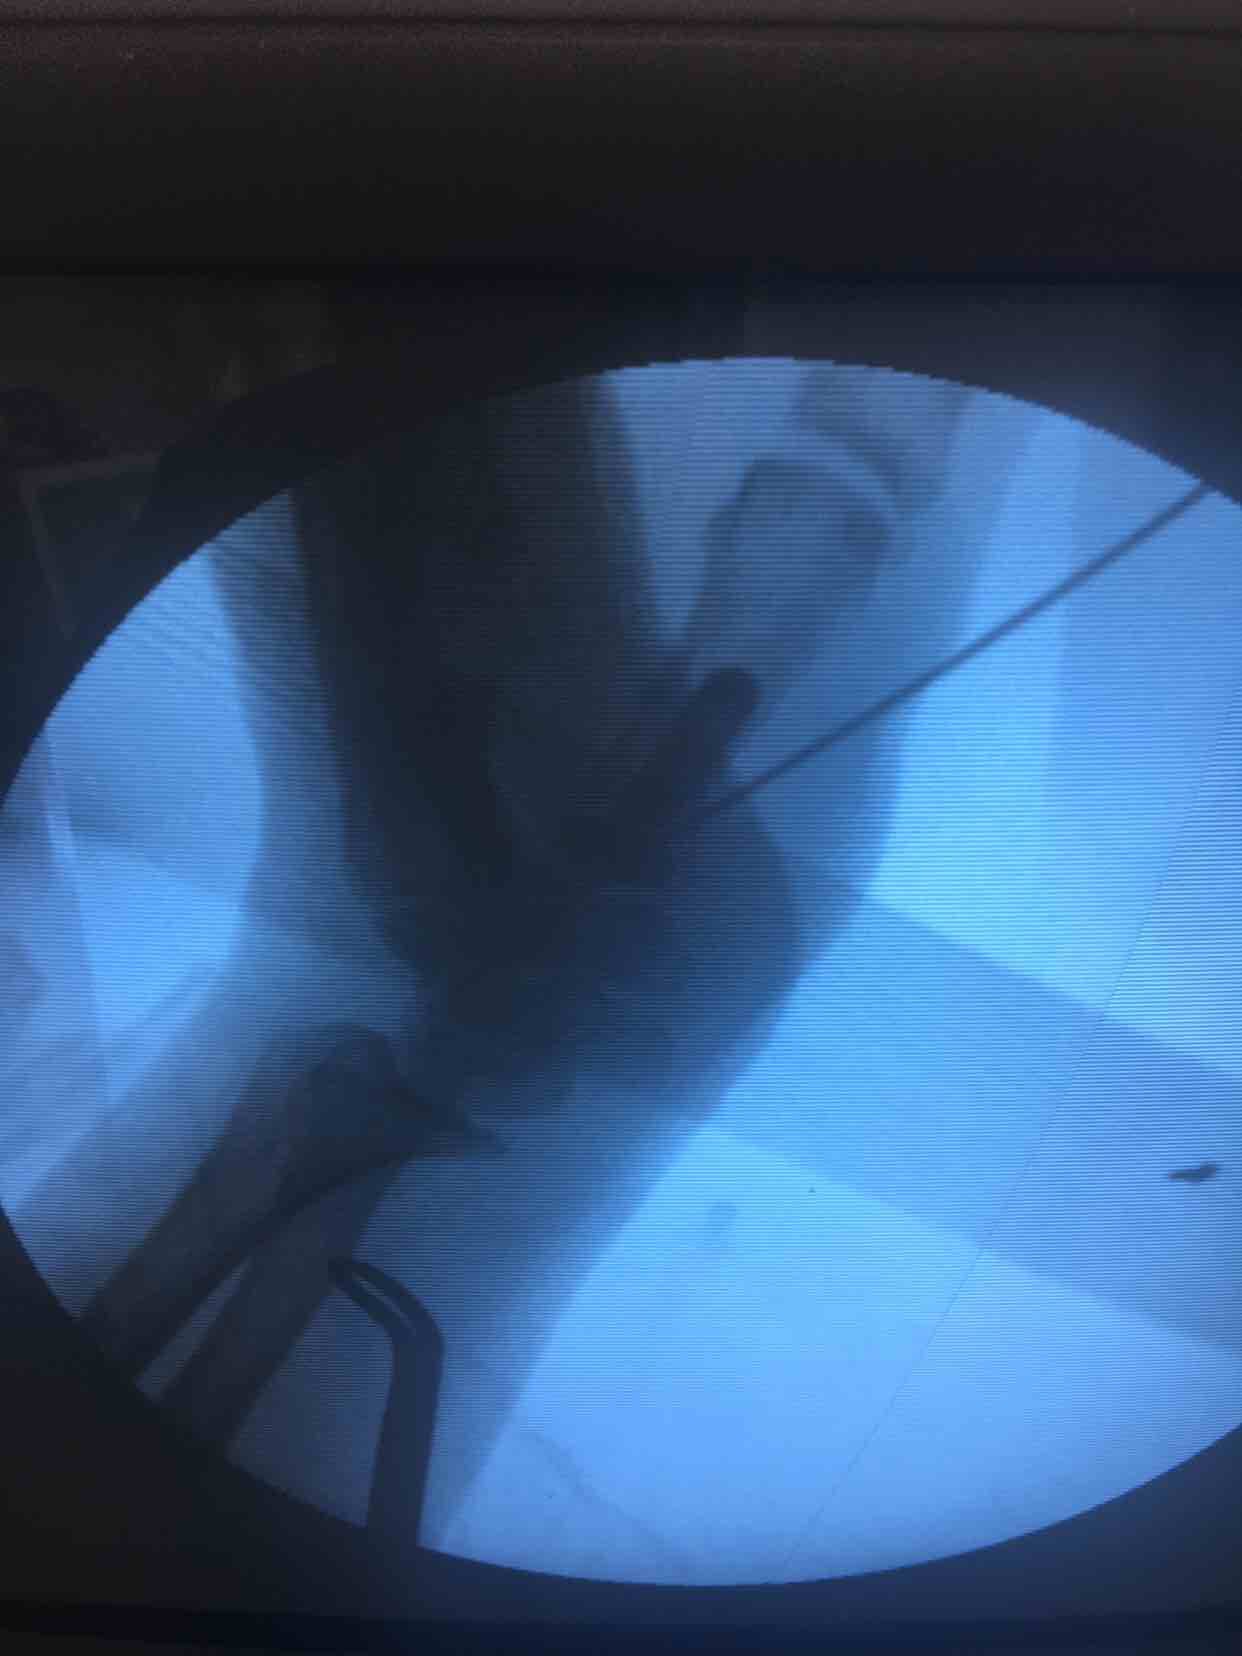

第一掌骨基底部骨折(微钢板固定)

诊断左手第一掌骨基底部骨折在臂丛麻醉下行切复内固定术,术后抗炎消肿等处理,石膏托外固定。